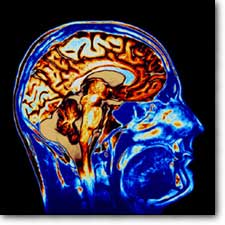

Göz testiyle MS teşhis edilebilecek

MS hastalığı artık basit bir göz testiyle teşhis edilebilecek. 'Optik uyum tomografisi' adlı yöntemle, gözün arkasındaki retina tabakasının kalınlığı ölçülüyor. Retinasında incelme olan hastalarda MS daha erken ve daha şiddetli. Böylece hastalığın seyri gözlemlenebiliyor.

Nöroloji dergisinde yayınlanan araştırmaya göre, optik uyum tomografisinin günlük tıp pratiğinde ne kadar kullanışlı olacağı henüz belli değil.

Tomografiyi 165 MS hastasına uygulayan John Hopkins Üniversitesi araştırmacıları denemelere devam ediyor.

Öngörülmesi hayli zor bir rahatsızlık olan MS'in belirtileri yok olup, haftalar, aylar sonra nüksedebiliyor. Tedavisi yok, ancak ilerleyişini yavaşlatmak mümkün.

Bilimadamları bu yüzden MS teşhisi için farklı yöntemler kullanmak istiyor. Ve, optik uyum tomografisi önemli bir alternatif olarak görülüyor. Böylece MS hastalığının ilerleyişini yavaşlatan terapilerin etkinliği de ölçülebilecek.